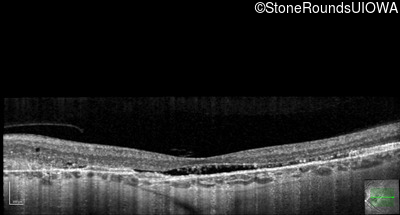

Optical Coherence Tomography - Left - 20/30 -2 sc

Exemplar / OCT Stack